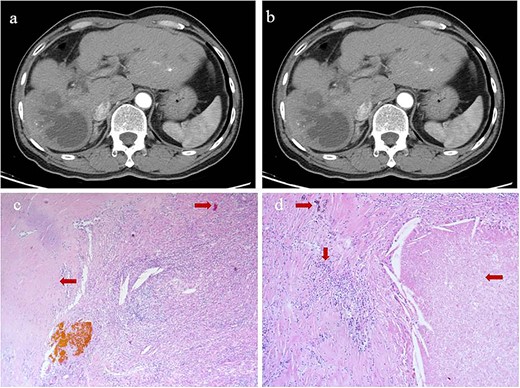

At 24 months after his admission with hepatic occupation, contrast-enhanced computed tomography detected intrahepatic recurrence, which was confirmed by magnetic resonance imaging. The patient was admitted again and given two cycles of transarterial chemoembolization (TACE), which achieved a partial response (PR) based on the Response Evaluation Criteria for Solid Tumors [18] (Fig. 2a and b). At 16 weeks after his second admission, the patient underwent right hemihepatectomy. Baseline variables before surgery are described in Supplementary Table 1. The surgery proceeded smoothly, and the patient recovered well. Postoperative histopathology revealed necrosis in more than 90% of the tumor, whereas no nodular cirrhosis, satellite nodules, or tumor emboli were observed. Instead, necrotic and proliferative fibrous tissue with multinucleated giant cells was observed, with abundant infiltration by lymphocytes and focal aggregation of neutrophils (Fig. 2c and d). Surrounding liver tissue showed chronic hepatitis changes (G2S2 on the inflammation and fibrosis scale) as well as hyperplasia of the small bile duct.

Intrahepatic recurrence and response to TACE. (a, b) Contrast-enhanced computed tomography in the (a) arterial phase or (b) venous phase after two cycles of TACE, showing PR of the recurrent tumor liver. (c, d) Histopathology of recurrent tumor after TACE at magnifications of (c) 40× or (d) 100×, showing necrosis of more than 90% of the tumor, proliferative fibrous tissue (leftward arrows), blue embolic agent in vasculature (rightward arrows), multinucleated giant cells, and abundant infiltration by lymphocytes (downward arrow).